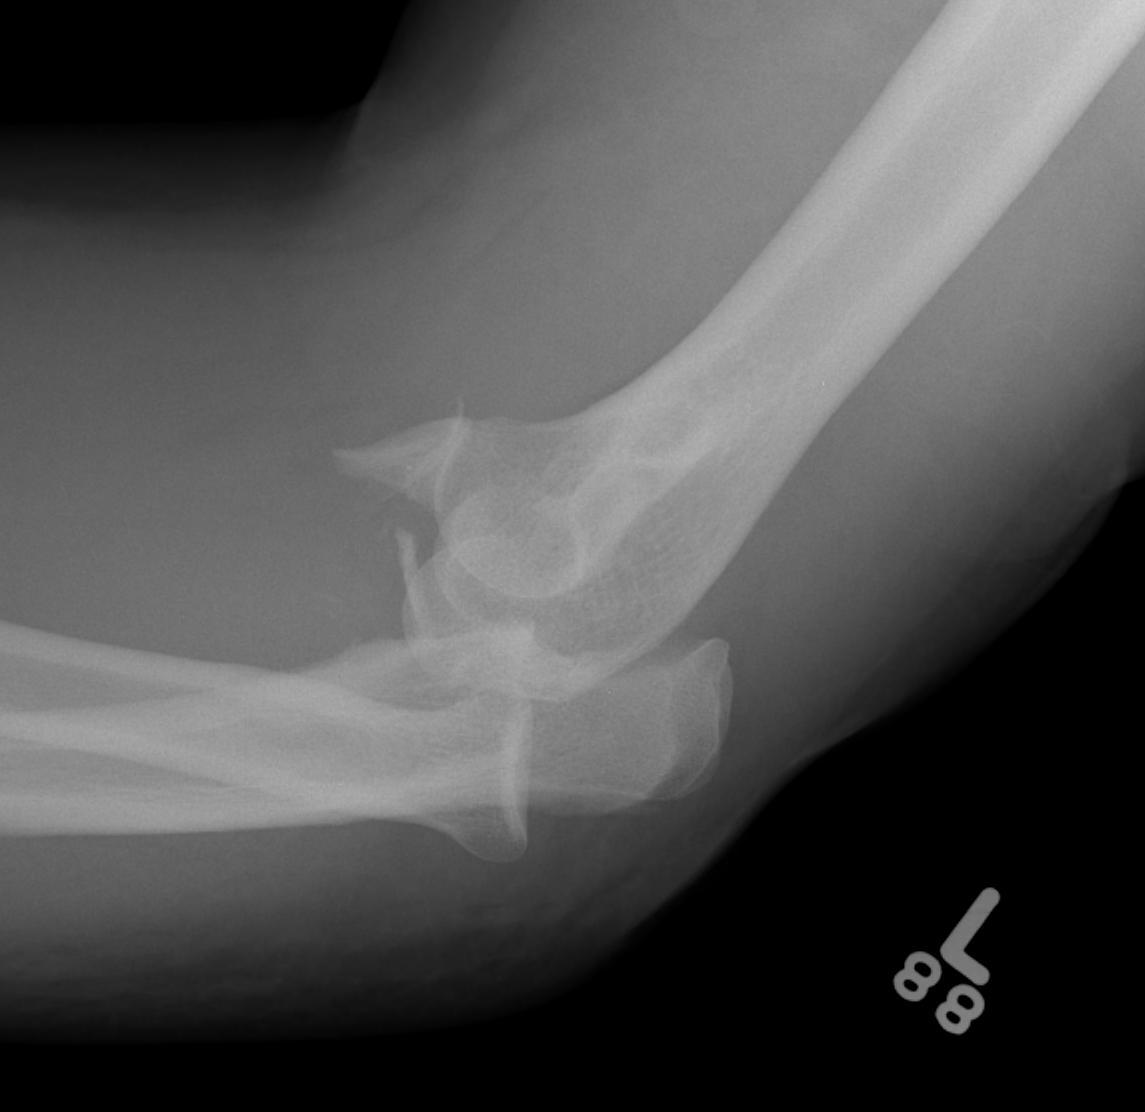

Terrible Triad

Definition

Elbow dislocation with radial head fracture + coronoid fracture + MCL tear

Technique

Surgical Algorithm

Principles

1. Restore coronoid stability - ORIF type II / III, suture repair type I

2. Restore radial head stability - radial head ORIF or arthroplasty

3. Restore lateral stability - LCL repair and common extensor origin +/- reconstruct +/- internal brace

4. +/- Restore medial stability - repair MCL if residual stability

5. +/- External fixation / internal joint fixation